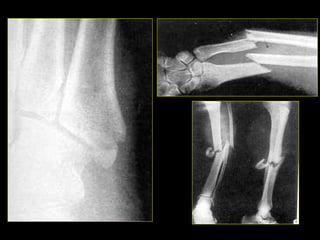

• #10 Fractura de la base del V metatarsiano (izq). Fx desplazada de cúbito y radio (sup-der); Fx desplazada tibia peroné.